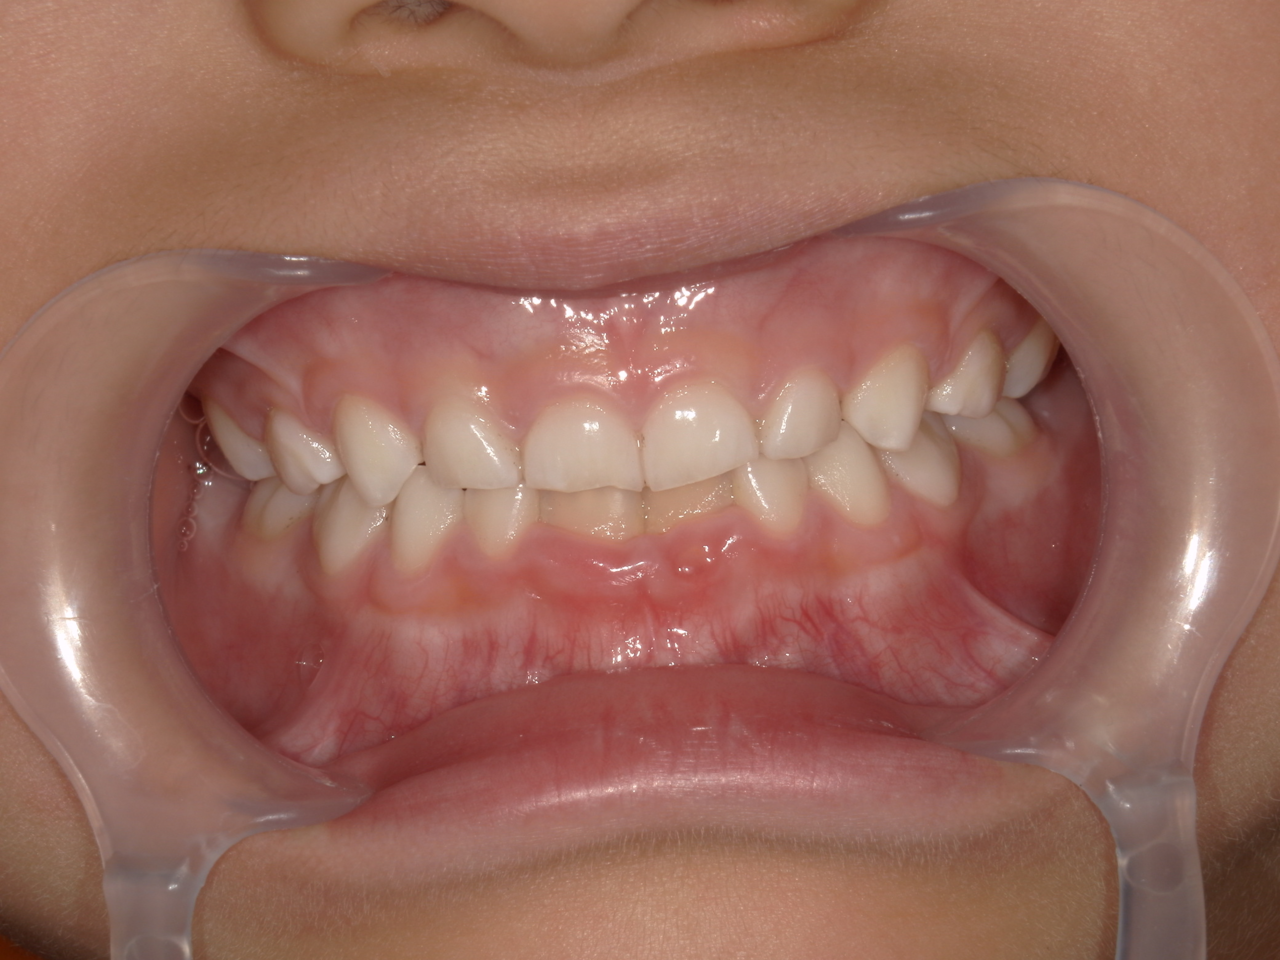

治療後

治療の副作用(リスク)歯の動き方には個人差があり、予想された治療期間が延長する可能性があります。。床矯正の使用状況、矯正歯科治療には患者さんの協力が必要であり、それらが治療結果や治療期間に影響します。2次矯正が必要になる場合もあります。